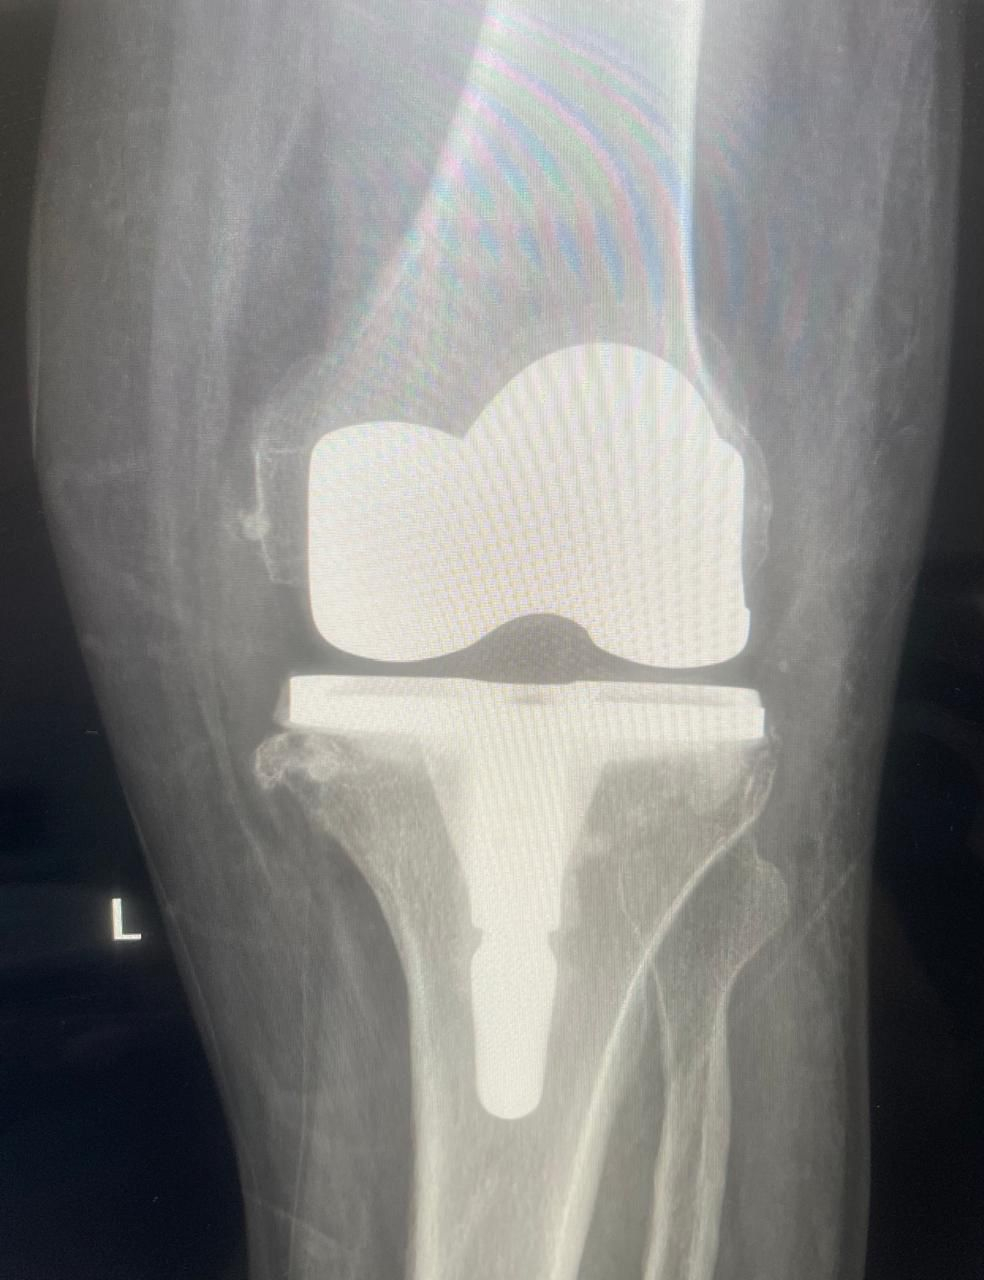

وكشف المستشفى أن الوحدة سجّلت منذ بدء تشغيلها تنفيذ 30 عملية ناجحة لتبديل مفصل الركبة، وفق أحدث الممارسات الطبية والمعايير العالمية المعتمدة، بما يعكس جاهزية الكوادر الطبية المؤهلة وتوفر التقنيات الجراحية المتقدمة داخل المستشفى.

وتقدّم الوحدة خدمات طبية متكاملة تشمل تقييم وتشخيص حالات تآكل المفاصل والإصابات المزمنة، وإجراء عمليات تبديل المفاصل باستخدام أحدث التقنيات الجراحية، إلى جانب تنفيذ برامج تأهيل وعلاج طبيعي متخصصة تسهم في تسريع تعافي المرضى وتحسين جودة حياتهم واستعادة قدرتهم على الحركة.